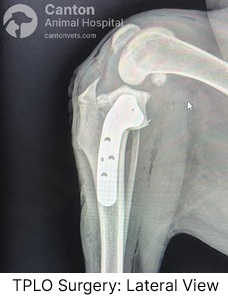

What is the TPLO procedure?

TPLO stands for tibial plateau leveling osteotomy. The Tibial Plateau Leveling Osteotomy (TPLO) is a widely used surgical technique to treat cranial cruciate ligament (CCL) injuries in dogs. It changes the knee’s biomechanics by altering the tibial slope, eliminating the need for the damaged ligament.

Gold standard for large-breed, active dogs.

Alters the tibial slope to eliminate instability without needing a new ligament.

Provides faster recovery and long-term success.

Advantages of the TPLO Procedure

Highly Effective for Long-Term Stability – Alters the knee’s biomechanics to restore function and reduce arthritis risk.

Best for Active & Large Breed Dogs – Provides strong, durable joint stability, ideal for working or athletic dogs.

Faster Return to Normal Activity – Many dogs start using the leg within days after surgery.

Lower Risk of Implant Failure – Well-studied with a high success rate in preventing future joint instability.

Reduces Arthritis Progression – Minimizes long-term joint deterioration compared to extracapsular repairs.

Disadvantages of the TPLO Procedure

Invasive Surgery – Requires cutting and repositioning the tibia, which may lead to more initial discomfort.

Longer Recovery Time – Full healing can take up to 12–16 weeks with strict post-op care.

Higher Cost – TPLO is more expensive than extracapsular repair techniques.

Potential for Complications – Risks include infections, bone fractures, implant loosening, or delayed healing.